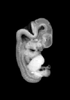

Carnegie Stage 20 (50 post-ovulatory days)

Most embryos at stage 20 are approximately 50-51 postovulatory days old and measure 21-23 mm in length. Distinguishing criteria for this stage include upper limbs slightly bent at the elbows, short stubby fingers, hands curving over the cardiac region but still far apart from each other, and a fringe-like vascular plexus that marks growth centers laterally in the superficial tissues of the head.

Although some of the photographs below show abnormal embryos, the animations and MRI slice images all depict normal embryos. Abnormal embryos are noted in the titles of the large photos when they are opened.